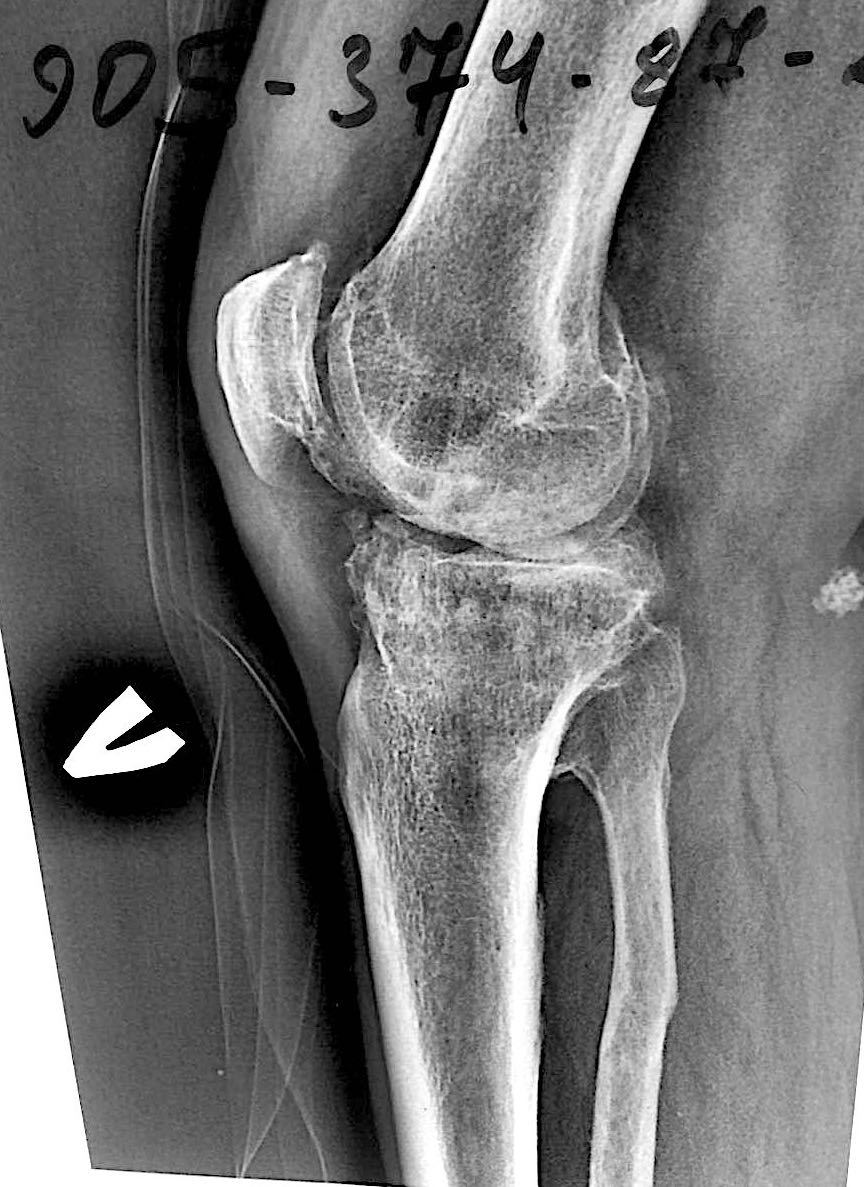

Больной З. 72 года. Диагноз: посттравматический деформириующий правосторонний гонартроз, genu valgum.

Сделано тотальное эндопротезирование коленного сустава, костная аллопластика материалом «Лиопласт».